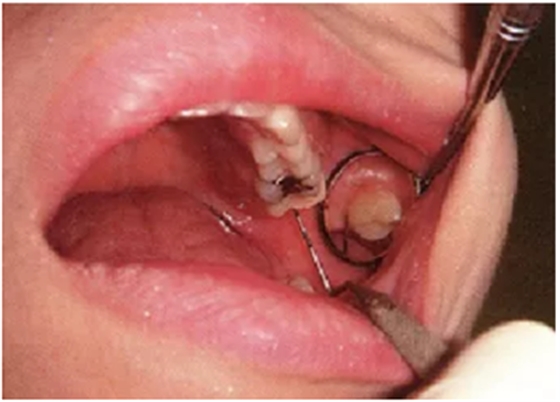

上颌第二后磨牙颊侧远中的检查技巧

上颌第二后磨牙的颊侧远中检查难度特别高。探针插入本身难度很高,还要读取数值,非常艰难。这个部位的检查页和上面颊侧检查一样让患者嘴巴微闭,利用口镜可以比较容易读取数值。

● 利用口镜对上颌第二后磨牙颊侧远中检查时,患者嘴巴也需要微闭。

微闭嘴巴,颊粘膜跟容易延展,将口径放入嘴巴时可以确保有充足的空间。